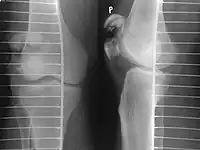

Diagnosis is based on symptoms and confirmed with X-rays.[3] In children an MRI may be required.[3]